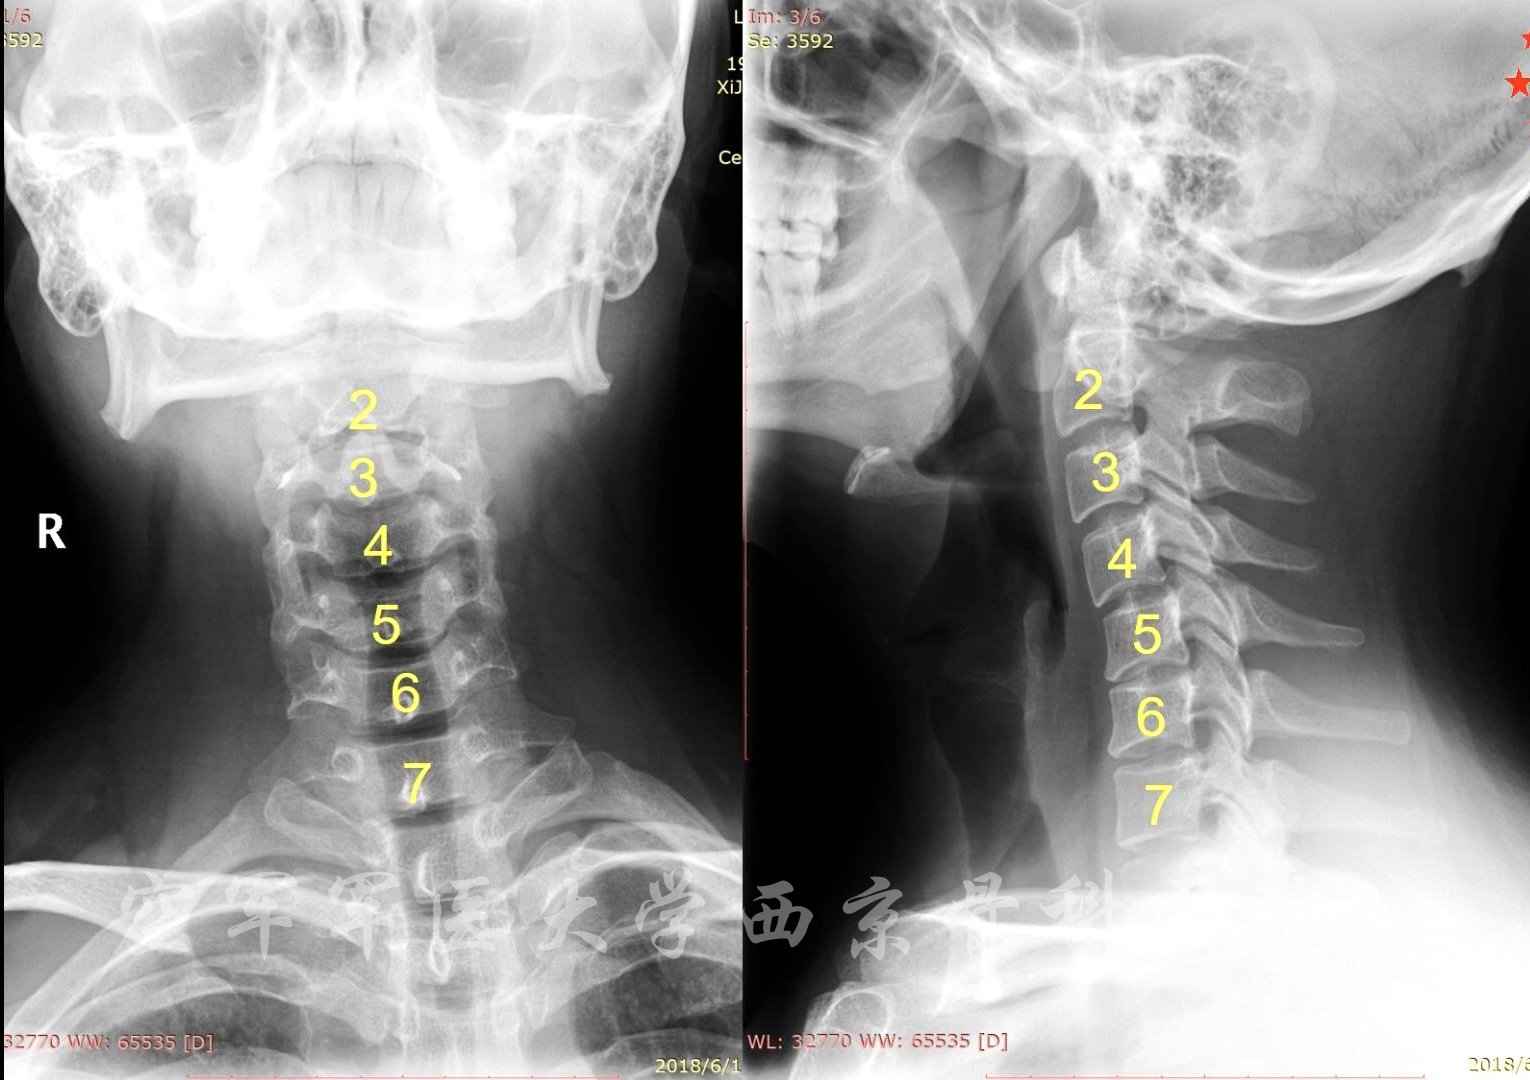

术前X线

术后X线正侧位片